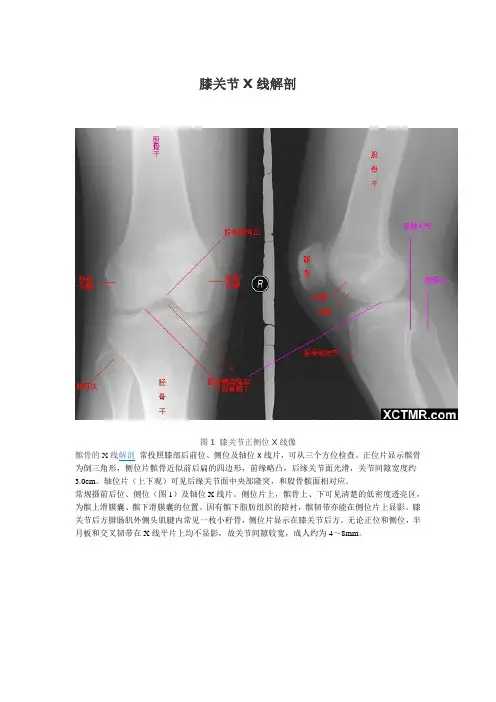

图1 膝关节正侧位X线像

髌骨的X线解剖常投照膝部后前位、侧位及轴位X线片,可从三个方位检查。

正位片显示髌骨为倒三角形,侧位片髌骨近似前后扁的四边形,前缘略凸,后缘关节面光滑,关节间隙宽度约3.0cm。

轴位片(上下观)可见后缘关节面中央部隆突,和股骨髌面相对应。

常规摄前后位、侧位(图1)及轴位X线片。

侧位片上,髌骨上、下可见清楚的低密度透亮区,为髌上滑膜囊、髌下滑膜囊的位置。

因有髌下脂肪组织的陪衬,髌韧带亦能在侧位片上显影。

膝关节后方腓肠肌外侧头肌腱内常见一枚小籽骨,侧位片显示在膝关节后方。

无论正位和侧位,半月板和交叉韧带在X线平片上均不显影,故关节间隙较宽,成人约为4~8mm。